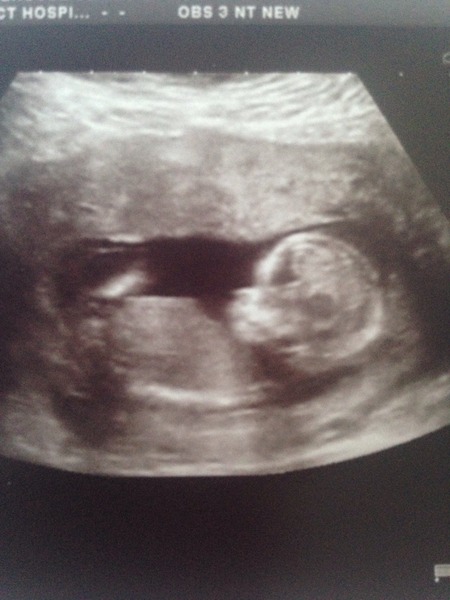

yaaay congratulations biffle and earlgrey .. Lovely scan pictures ...

Emma ... Mine took about 30 minutes, mainly because the baby was camera shy and wouldn't lie on its side for a proper NT measurement so the sonographer had to make me jump up and down and jiggle around to get the baby moving. The main things they do is measure the baby to check your due date (its not always the most accurate by LMP. I got moved 3 days) .. They check the fluid at the back of baby's neck to see if there is a higher risk of downs, edwards and pataus and do a quick limb and head count to make sure everything is as it should be.